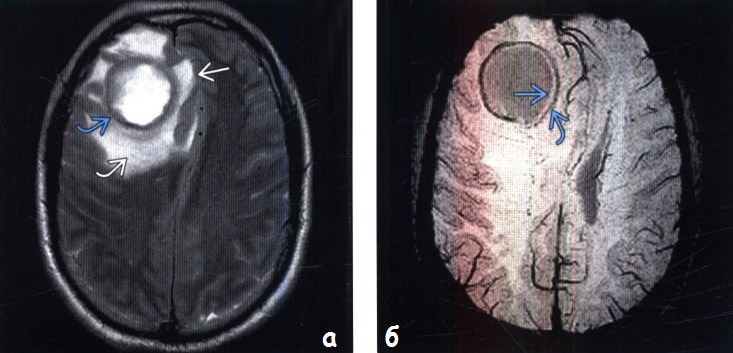

| Abcesul cerebral | DEFINIȚIE ȘI CAUZEAbcesul cerebral reprezintă o colecție de puroi conținută într-o cavitate neoformată, rezultând în principal din necroza unei zone tisulare consecutivă inflamației.

Abcesele cerebrale sunt considerate procese expansive intracraniene și sunt datorate acțiunii bacteriilor, fungilor sau paraziților. Jumătate din cazuri sunt complicații ale otitelor și sinuzitelor. MANIFESTARI CLINICETabloul clinic de abces cerebral variază în limite destul de largi și depinde în principal de sediul hematomului, de mărimea acestuia, de vârsta pacientului și de patologia asociată.